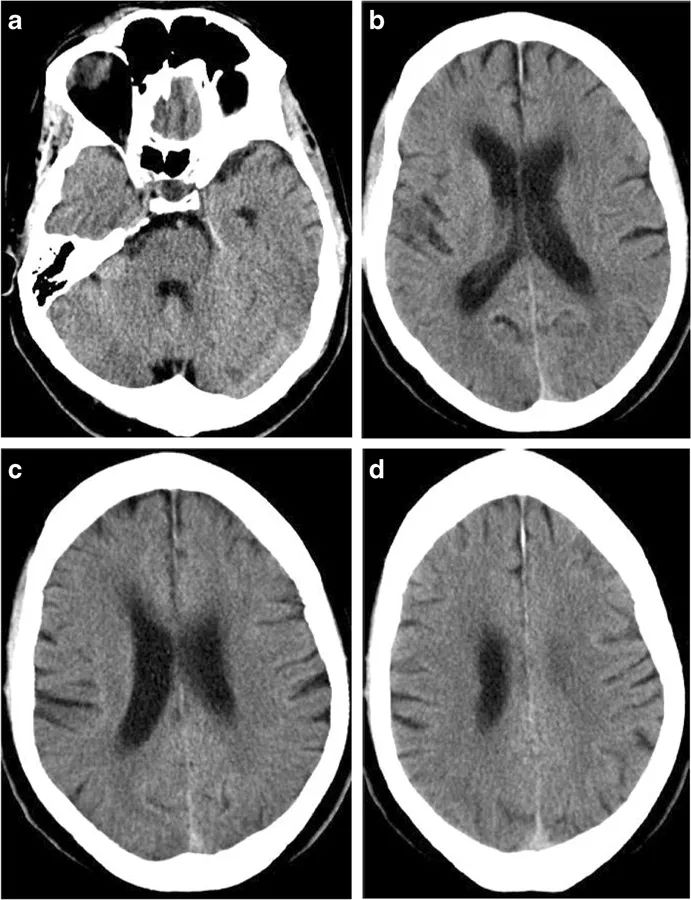

图2 恶性脑梗死的进展过程。在卒中发病的6小时内,CT仅显示额叶、岛叶皮质、颞叶、尾状核和豆状核的轻度密度减低(左);12小时后,可见大脑中动脉和大脑前动脉供血区域边界清晰的梗死区域(中);但没有占位效应。24小时后,病灶出现占位效应,中线移位(右)。